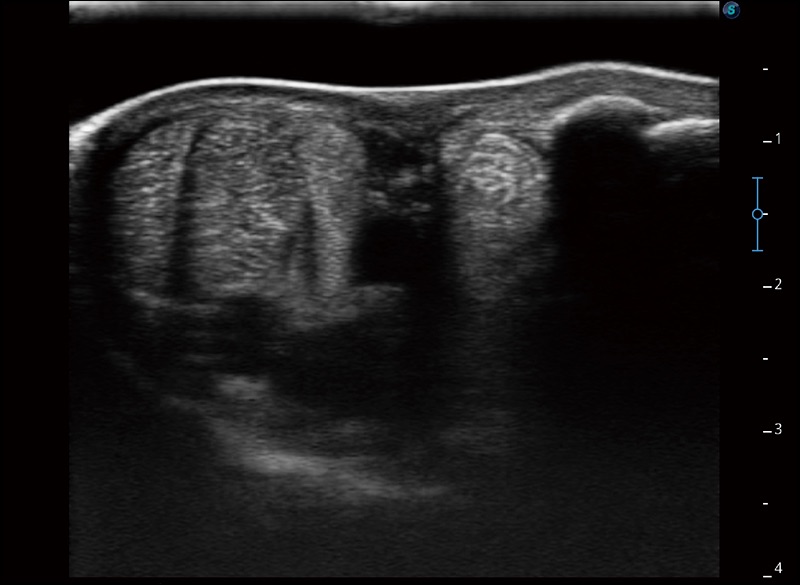

α1卓越的图像质量和便捷的工作流程,使每位宠物医生都能轻松扫查。其全面的兽用应用功能和紧凑型的结构设计,可以满足动物检查的多种需要。专业的预设检查模式和多领域测量软件包有助于为不同类型的动物提供检查, 让宠物医生能够出色的完成工作。

穿刺针增强

高清显示穿刺进针情况

连续波多普勒成像CW

为心脏功能评估提供更多诊断信息